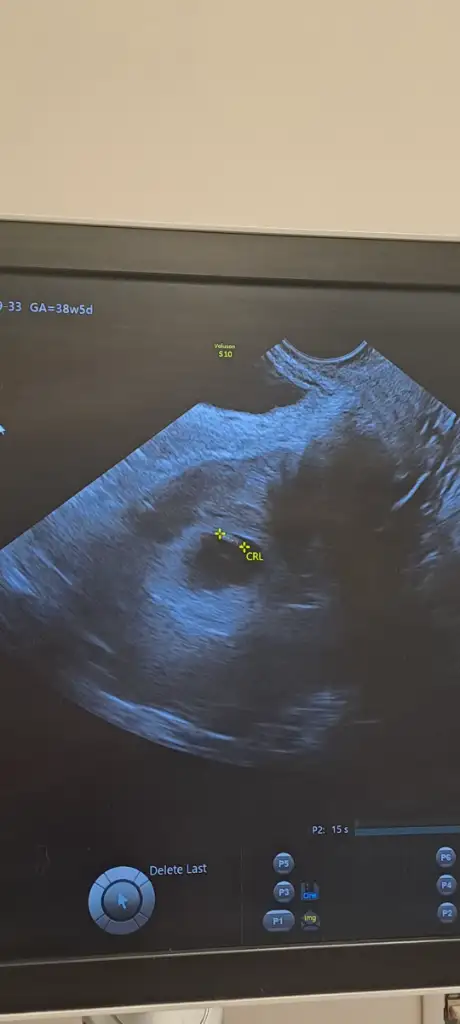

6 haftalık vajinal ultrason görüntüsü bize de bakabilir misiniz lütfen teyzeleri, teşekkür ediyorum şimdidenKızlar bebişlerinizin ultrason resimlerini ve cinsiyetini kaçıncı haftada olduklarını yazında kendi ultrason resimlerimizle kıyaslayıp fikirde bulunalım. Nub teorisi, kafa şekli, kemik yapısından cinsiyet teorileri tutuyor mu bakalım bir

6 haftalık vajinal ultrason görüntüsü bize de bakabilir misiniz lütfen teyzeleri, teşekkür ediyorum şimdidençok küçük ama kese kız gibi

6 haftalık vajinal ultrason görüntüsü bize de bakabilir misiniz lütfen, teşekkür ediyorum şimdidenKız gibi erkeğin kesesi genelde fasulyeye benziyo

6 haftalık vajinal ultrason görüntüsü bize de bakabilir misiniz lütfen, teşekkür ediyorum şimdidenkız gibi